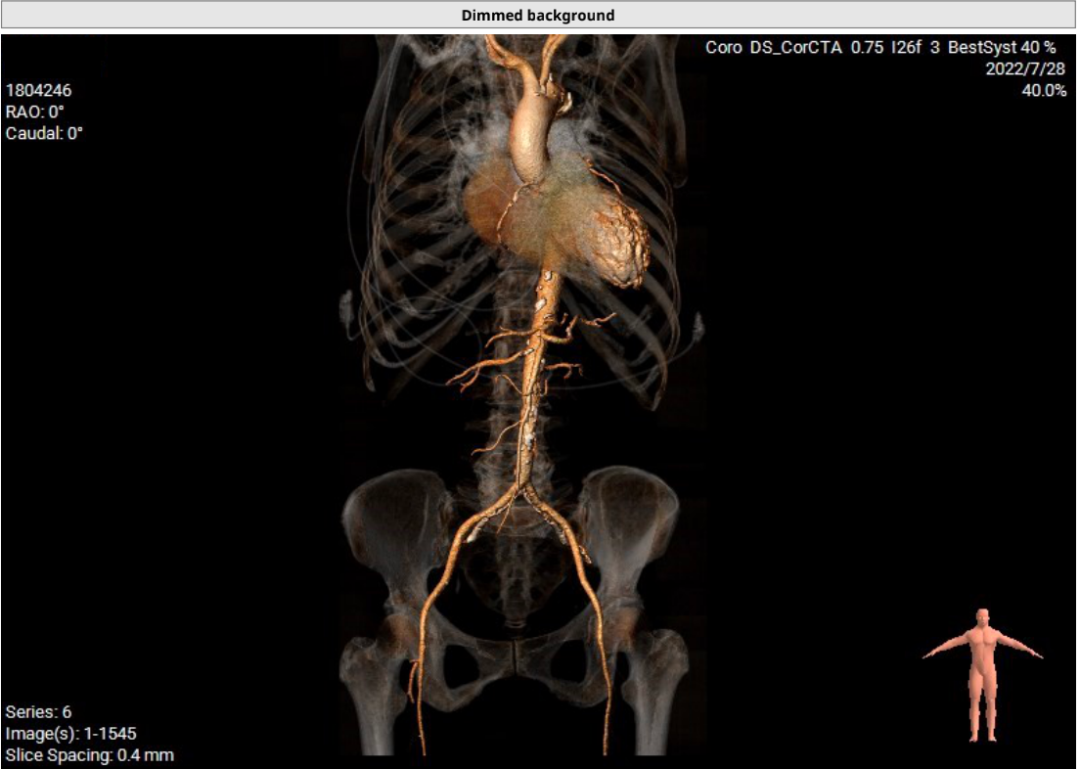

患者71岁女性,诊断为主动脉瓣重度狭窄合并心功能不全,瓣口面积仅0.5cm²,跨瓣压差超过50mmHg,且EF仅27%,心功能极差。术前CT检查瓣环周长72.2mm,LVOT呈喇叭型。CT检查同时发现患者入路血管狭窄,股动脉直径5.3cm,锁骨下和颈内动脉直径都小于5.0cm,对操作造成了一定困难。

患者64岁男性,Type 0 型二叶瓣、横位心。主动脉瓣中度狭窄,重度反流,瓣环周长92.0mm,平均径29.0mm。LVOT周长98.7mm,升主扩张,窦部结构极限,锚定能力极限。入路两侧血管轻度迂曲,分叉高度可,两侧血管内径均>8mm。